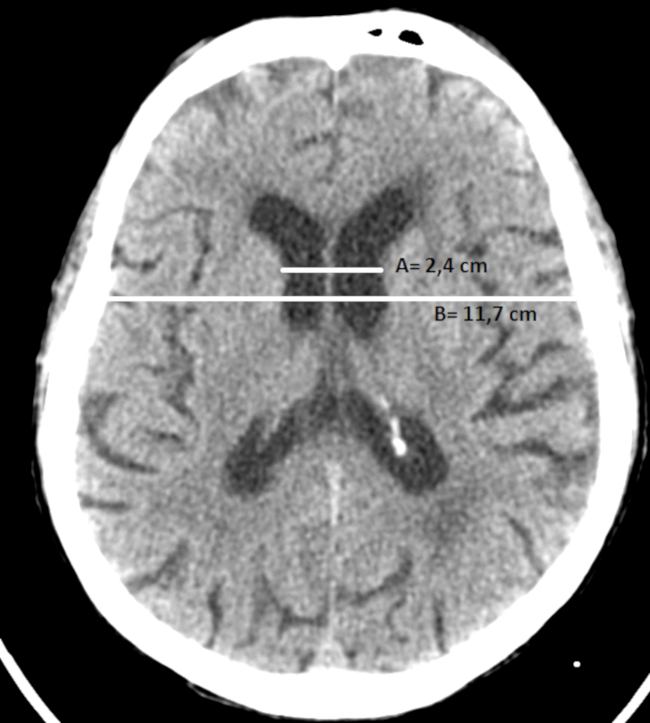

Los índices bicaudado, de Evans y bifrontal se obtienen en cortes axiales de TC y RM con orientación orbito-meatal, utilizándose para mesurar el envejecimiento fisiológico y cuantificar el grado de atrofia cerebral (►Tablas2,3y4).22,23,24

A) Índice bicaudado: se obtiene dividiendo la distancia mínima de los ventrículos laterales a nivel de las cabezas de los núcleos caudados con el diámetro del cráneo a ese mismo nivel (►Fig. 4).

B) Índice de Evans: se calcula dividiendo el diámetro máximo de las astas frontales de los ventrículos laterales con el diámetro máximo intracraneal en el mismo corte a la altura de los forámenes de Monro (►Fig. 5).22,23,24

Un valor > a 0,30 indica ventriculomegalia y puede considerarse patológico, pero no puede discriminarse la etiología por atrofia u otra entidad.22,23,24

C) Índice bifrontal: se calcula dividiendo el diámetro máximo de las astas frontales de los ventrículos laterales y el diámetro intracraneal a ese mismo nivel (►Fig. 6).22,23,24